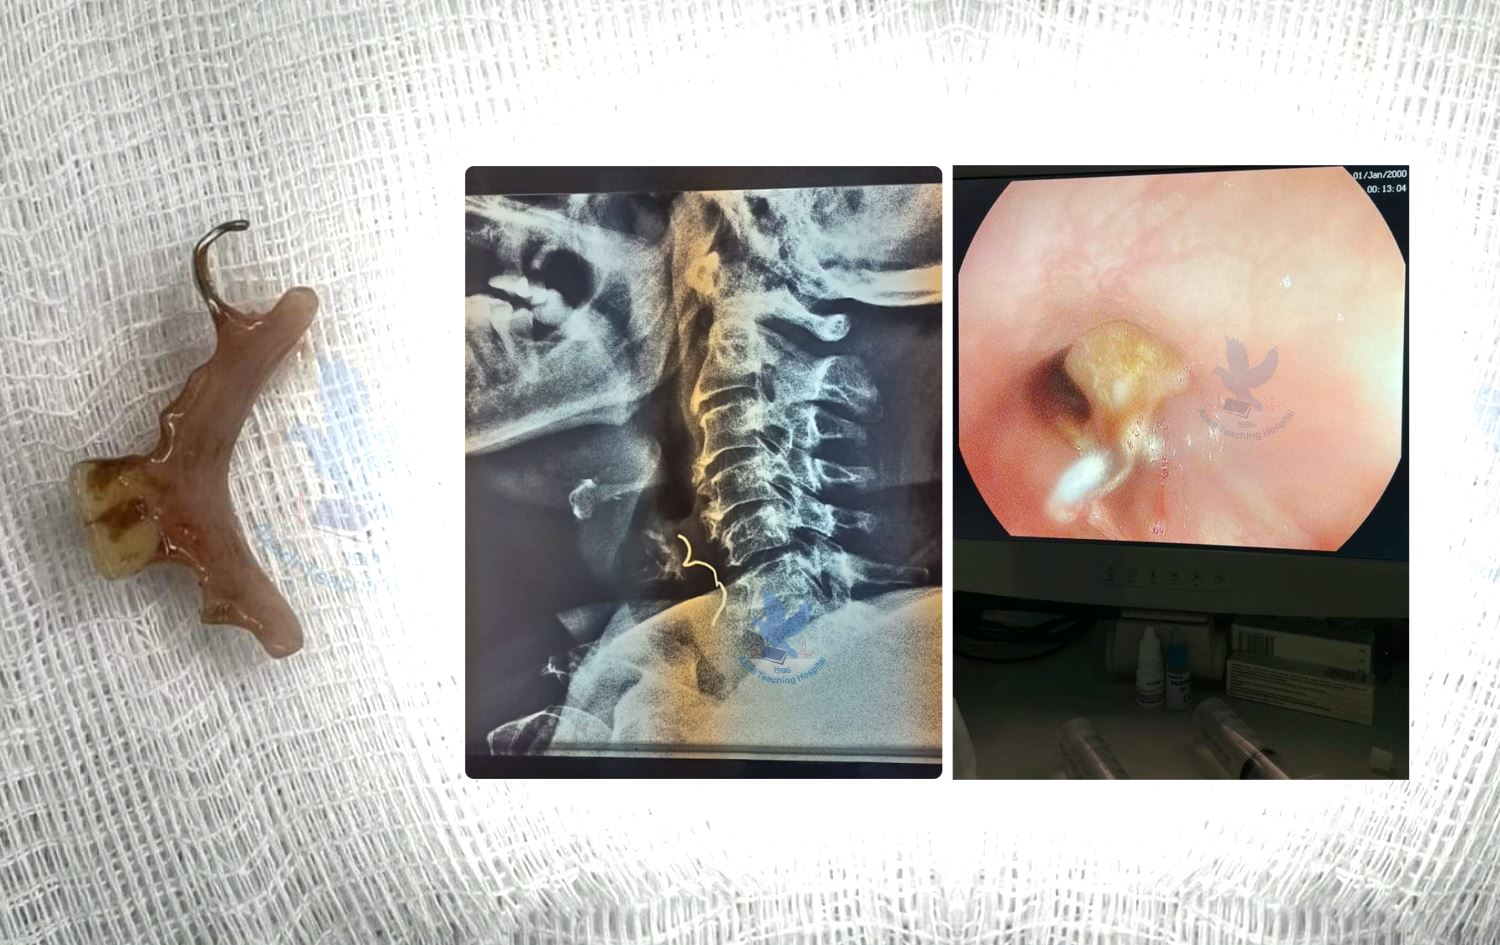

لە بەشی ھەناوبینیی نەخۆشخانەی ئازادی لە دهۆک پردێکی ددان لە بۆڕیی خواردنی ئافرەتێکی تەمەن 60 ساڵ دەرھێنرا.

رۆژی یەکشەممە، 14ـی ئایاری 2023، نەحۆشخانەی ئازادی لە تۆڕی کۆمەڵایەتی فەیسبووک بڵاویکردەوە کە ئافرەتێکی تەمەن 60 ساڵ، سەردانی بەشی ھەناوبینیی نەخۆشخانەکە کردووە، لەبەر ئەوەی پردی ددانەکانی قوت دابوو، چووبووە ناو بۆڕیی خواردن (سورێنچک).

نەخۆشخانەکە چەند وێنەیەکی بڵاوکردووەتەوە کە پردی ددانەکە پێشاندەدات و جێگەی دوو ددانی پێوەیە و دەڵێت توانیویانە بەھۆی دەزگای ھەناوبینی (نازووڕ) ئەو پردە بە سەرکەوتوویی دەربێنن و ئێستا تەندروستیی نەخۆشەکە جێگیرە.

بێوار شوکری، بەرپرسی راگەیاندنی نەخۆشخانەی ئازادی بە تۆڕی میدیایی رووداوی راگەیاند، تەندروستیی ئافرەتەکە باشە و رەوانەی ماڵەوە کراوە.